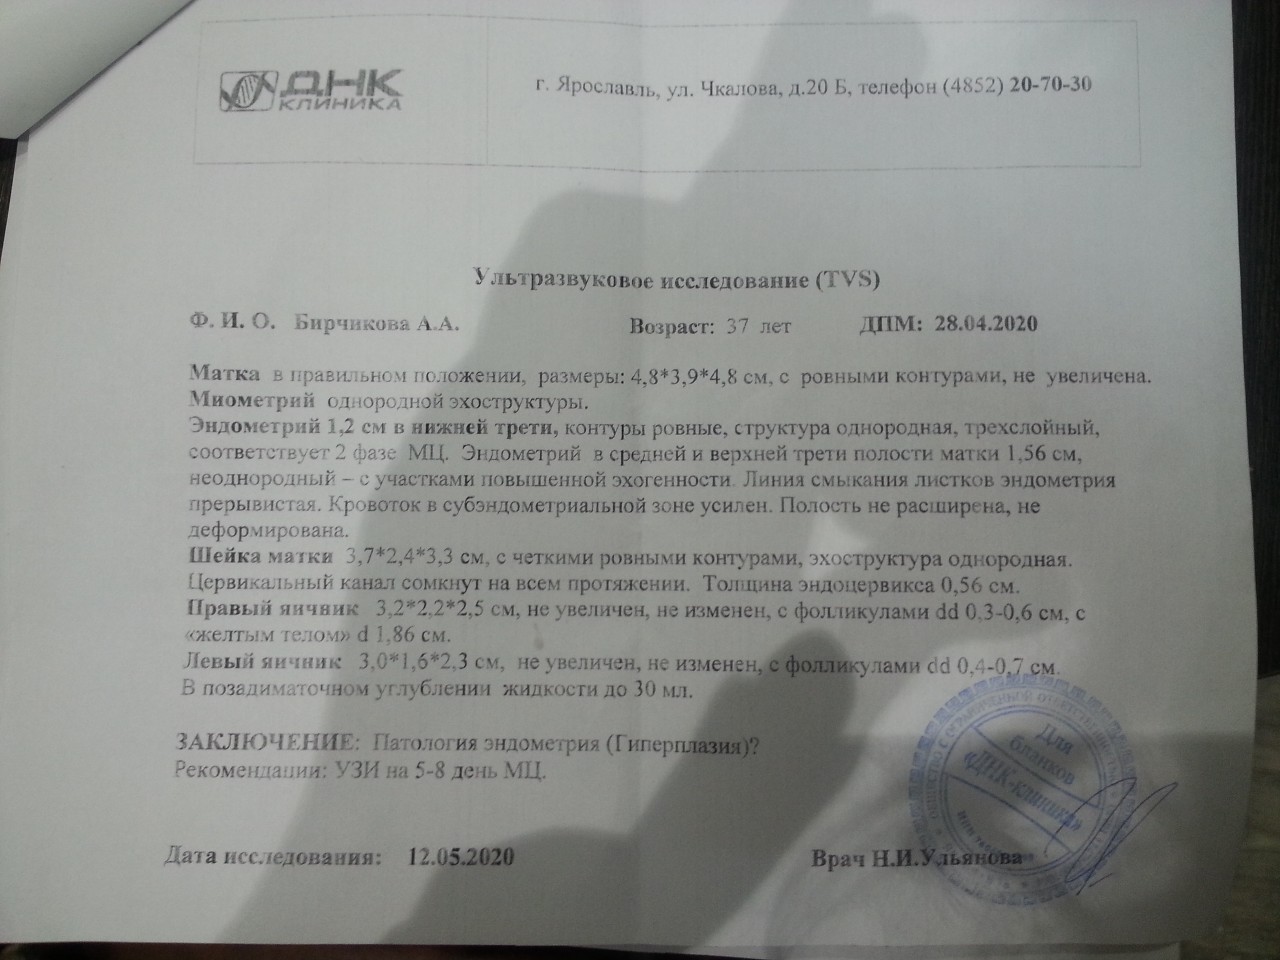

Медицинская диагностика: Гиперплазия эндометрия на УЗИ

Раздел: Мудрость в объективе